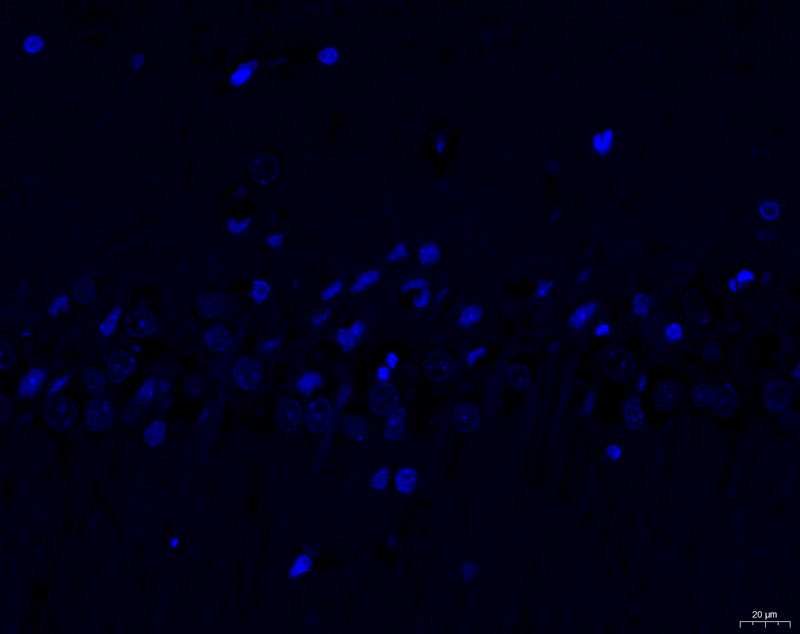

模型組1-1-40X-DAPI